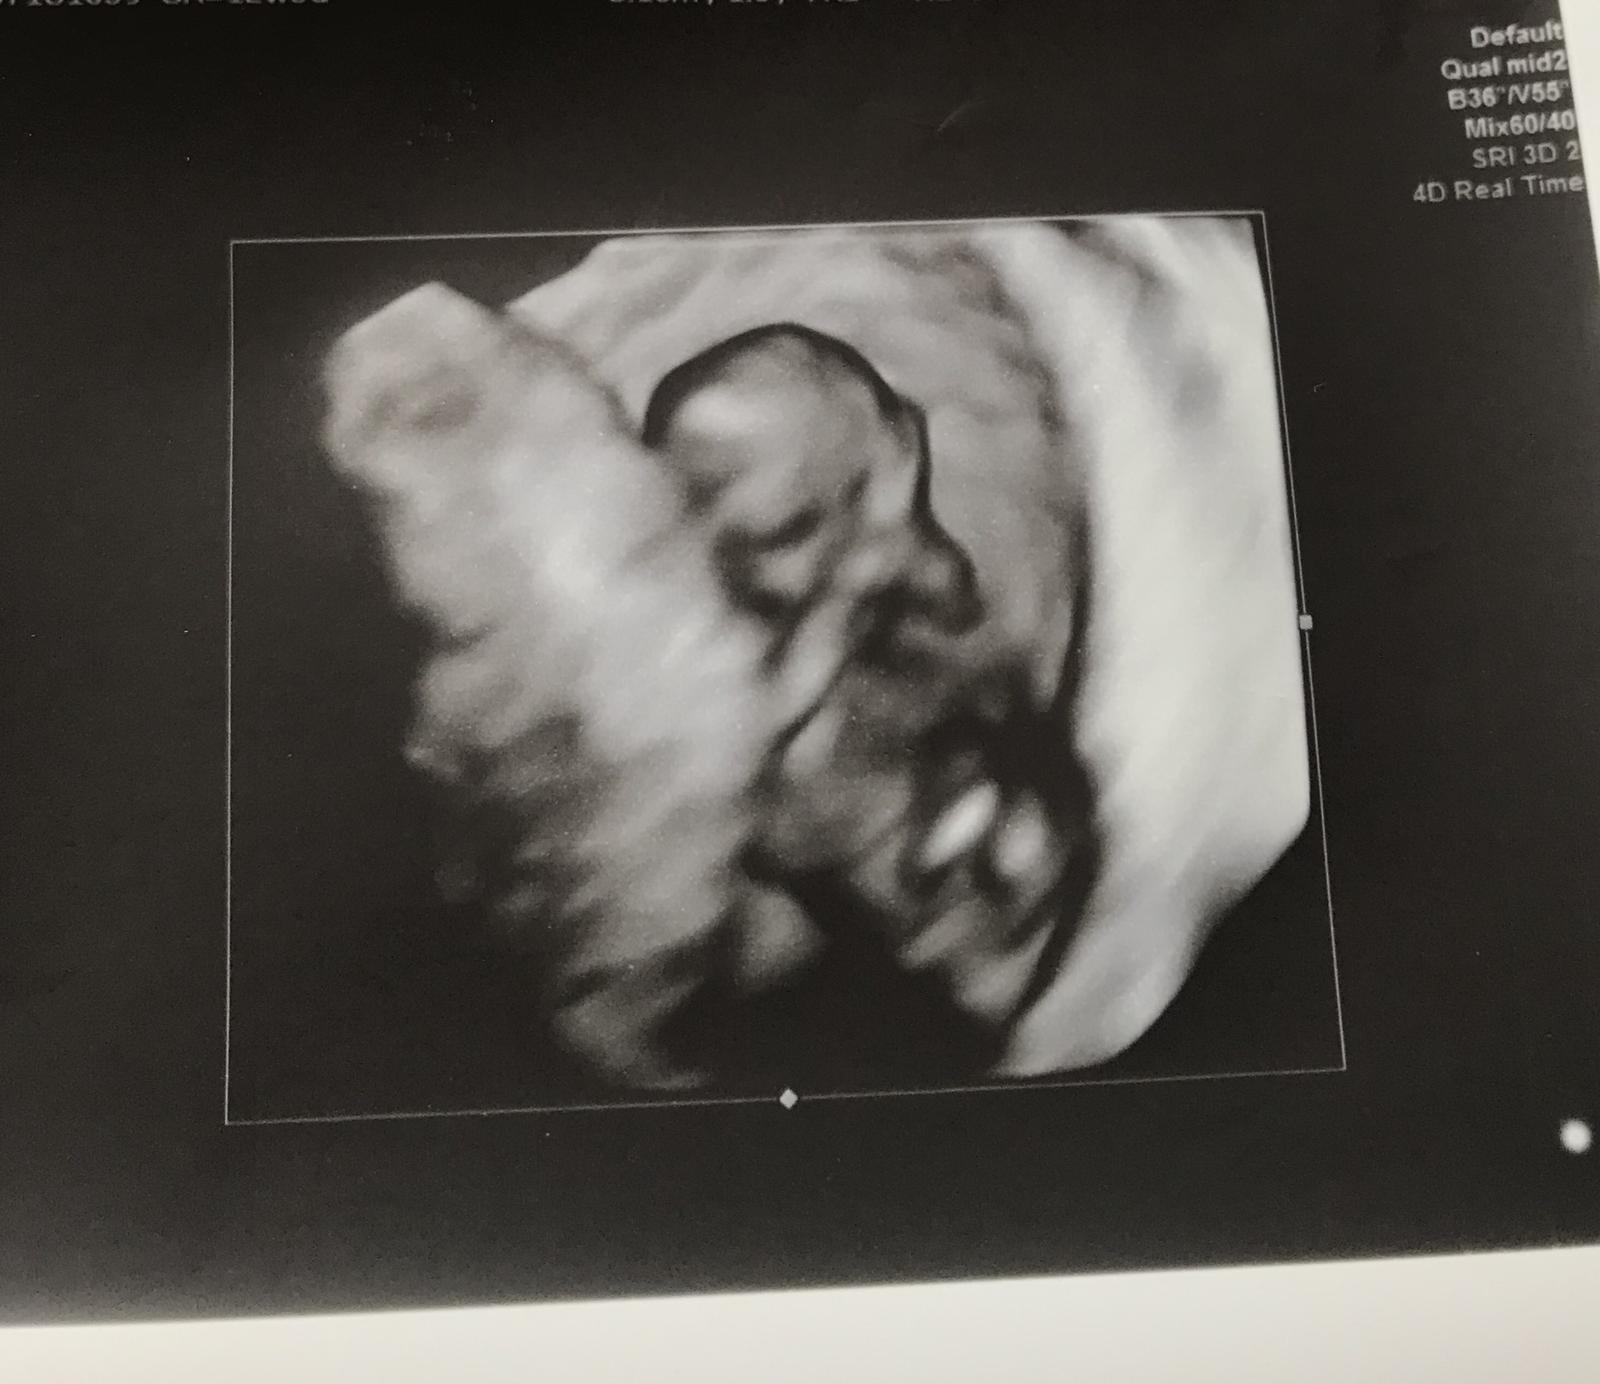

@mini007 kraaaasne